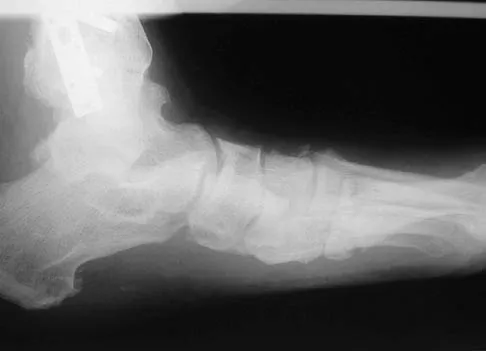

A 42-year-old man has a symptomatic flatfoot deformity and walks with a slight limp after falling off a scaffold 9 months ago. He also reports that he has had difficulty returning to work. Orthotics have failed to provide relief. Current radiographs are shown in Figures 19a and 19b. To relieve his pain and return the patient to work, treatment should consist of

Explanation

Because the patient has sustained a tarsometatarsal injury with midfoot sag, the treatment of choice is a tarsometatarsal arthrodesis. The cause of his flatfoot deformity is secondary to the tarsometatarsal injury and not from posterior tibialis tendon deficiency. Lateral column lengthening, double arthrodesis, and calcaneal osteotomy are not indicated. Although open reduction and internal fixation may be performed late when arthritis is present, these procedures are less likely to succeed. Komenda GA, Myerson MS, Biddinger KR: Results of arthrodesis of the tarsometatarsal joints after traumatic injury. J Bone Joint Surg Am 1996;78:1665-1676.